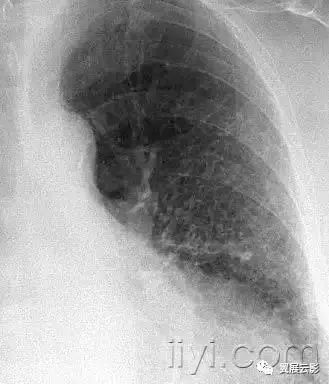

小叶中心性异常包括(1)结节(2)树芽征,提示小气道病变(3)由于临近间质的增厚或者浸润导致小叶中心结果更加清晰(4)小叶中心性肺气肿导致的异常低密度。

附图为小叶中心性肺气肿